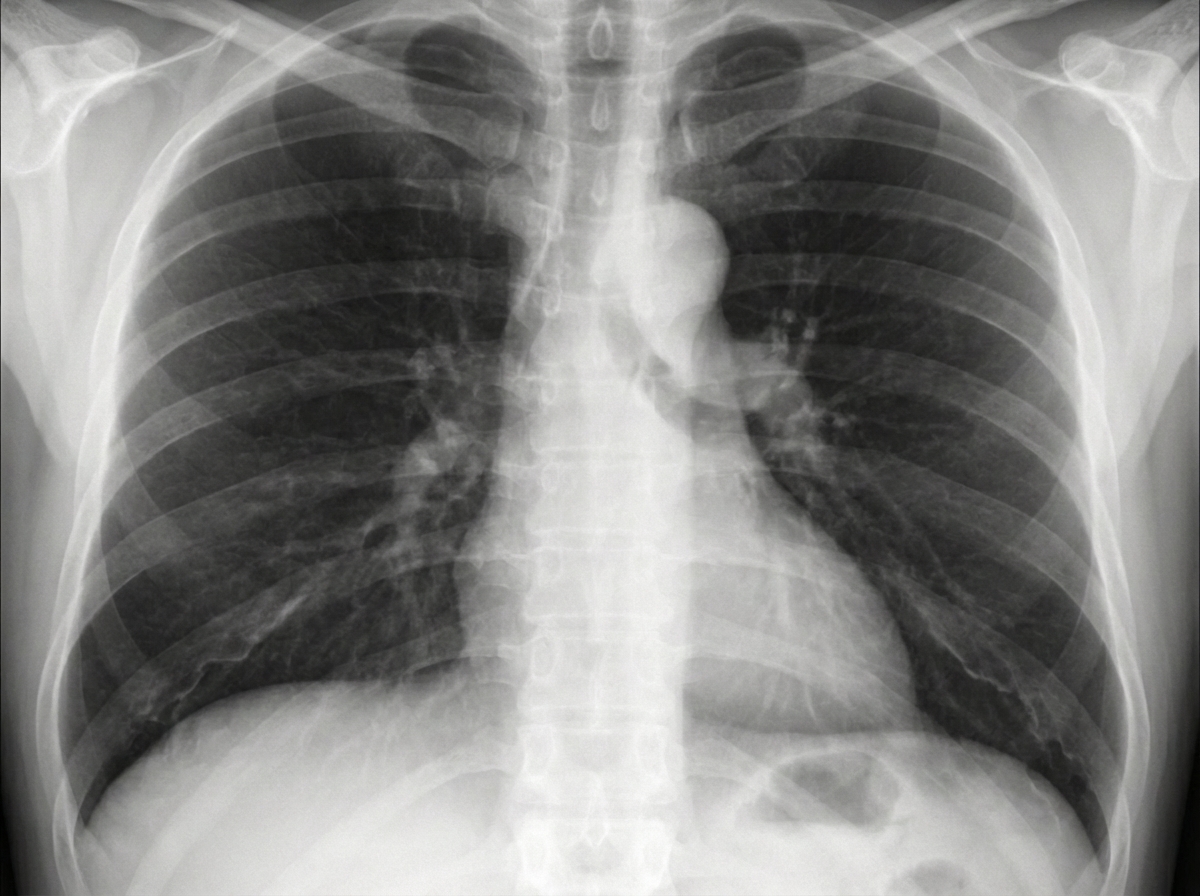

A patient presents with chest pain. What is the diagnosis?

Explanation: ***Ascending aortic aneurysm*** - Chest X-ray shows **widened mediastinum** and **prominent right paracardiac border** due to dilatation of the ascending aorta. - Often presents with **chest pain** and may cause compression of surrounding structures, leading to characteristic radiological findings. *Acute pulmonary embolism* - Chest X-ray is typically **normal** or may show subtle signs like **Westermark sign** (oligemia) or **Hampton's hump** (wedge-shaped opacity). - Diagnosis primarily relies on **CT pulmonary angiogram (CTPA)** or **V/Q scan**, not chest X-ray findings. *Hypertrophic cardiomyopathy* - Chest X-ray may show **left ventricular enlargement** with a **boot-shaped heart** configuration. - Lacks the characteristic **mediastinal widening** seen with aortic pathology, instead showing cardiac silhouette changes. *Coarctation of the aorta* - Chest X-ray demonstrates **rib notching** due to collateral circulation and **figure-of-3 sign** from pre- and post-stenotic dilatation. - Shows **left heart enlargement** but lacks the prominent right paracardiac border characteristic of ascending aortic aneurysm.